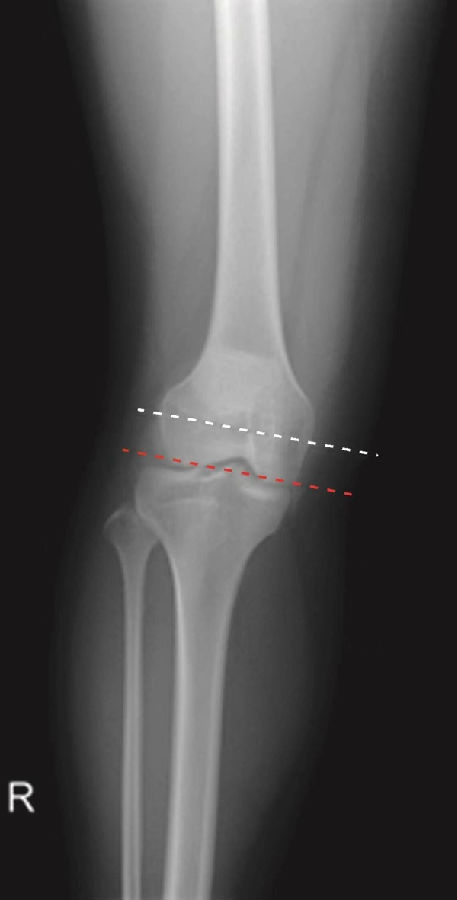

正常髌骨下极位于两侧股骨髁最低点连线之上,其下极在该连线近侧(图4)。髌骨高度大于其正常范围的最大值称为高位髌骨(图6),髌骨高度小于其正常范围的最小值称为低位髌骨(图5)。

图5 低位髌骨的正位X线片,髌骨下极位于两侧股骨髁最低点连线之下